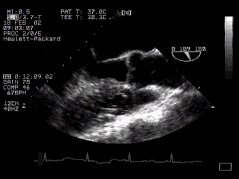

1. Two chamber view (LA, LV, MV) - 'ME 2 Chamber'

2. thumbnail ME SAX Longitudinal mid oesophageal 2 chamber view CLICK FOR VIDEO: mid oesophageal 2 chamber view  (longitudinal)

The left ventricular cavity and mitral valve are well seen. "Fine tuning" by careful probe movement can be used to demonstrate the papillary muscles and details of the mitral valve leaflets. (Inferior papillary muscle on your left, anterior on the right).